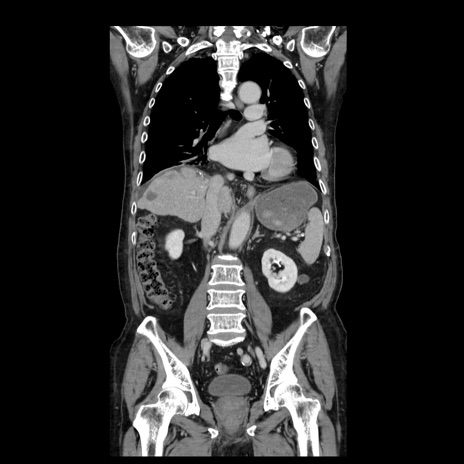

症例21(冠状断像)

【症例】70歳代男性

【主訴】腹痛

【現病歴】肝硬変・肝細胞癌にてかかりつけの方。約9時間前に食後より腹痛出現。症状が徐々に増悪し、嘔吐出現したため来院。

【既往歴】肝硬変、肝細胞癌(RFA、TACE後)

【身体所見】意識清明、表情苦悶様、BT 36℃、BP 129/78mmHg、P 88bpm、SpO2 97%(RA)、右上腹部から心窩部にかけて圧痛あり、反跳痛なし、筋性防御あり。

【データ】WBC 5800、CRP 0.16